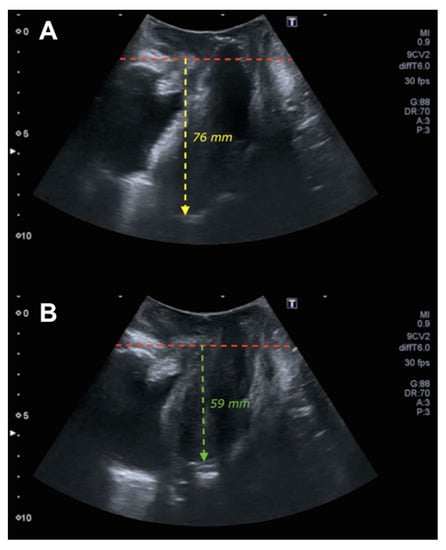

| Pubis–uterine fundus measurement | ||||

| Rest | −66.3 ± 12.8 | −74.8 ± 16.8 | 0.008 | 2.3; 14.6 |

| Valsalva | −41.2 ± 14.8 | −67.9 ± 17.3 | <0.0005 | 20.5; 33.0 |

| Pubis–uterine fundus measurement. Difference between rest and Valsalva | 25.1 ± 11.7 | 6.8 ± 4.4 | <0.0005 | 15.2; 21.5 |